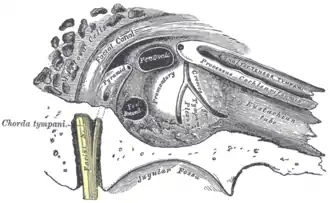

Vue de la paroi interne du tympan. La fenêtre du vestibule est l'ovale situé en haut.